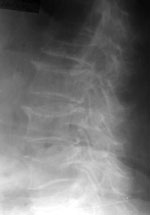

2. Двояковогнутая деформация — или деформация по типу «рыбьих позвонков» — снижение центральных отделов позвонков (hА/hР и hP/hPn не изменены, уменьшен hМ/hР) (Рис. 2).

[Увеличить]

Рис. 2. Двояковогнутая деформация LIV.